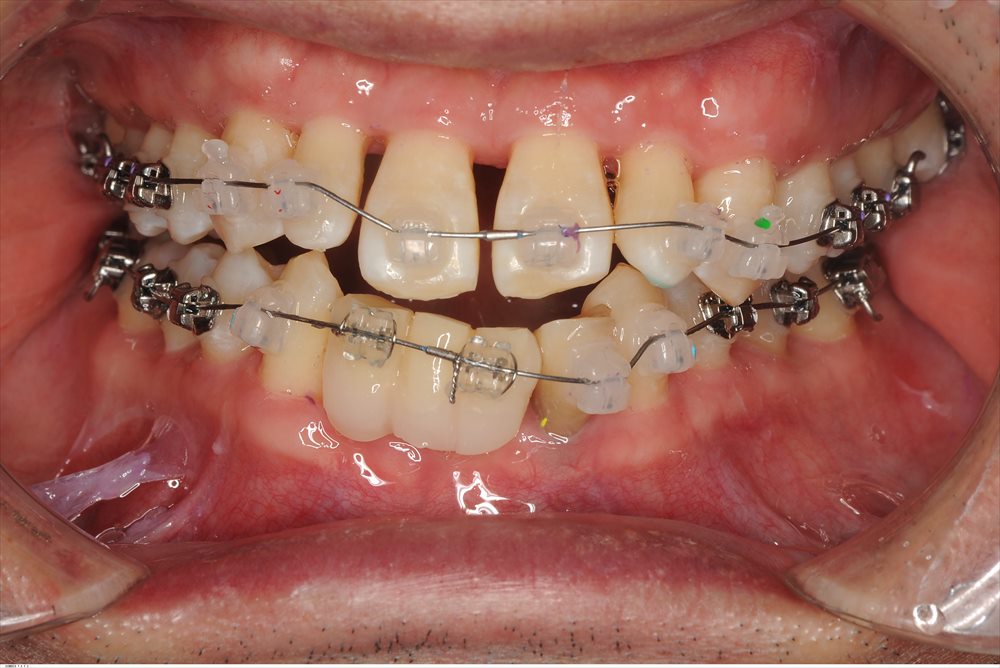

かみ合わせの問題もあり調整を行い

歯周初期治療(MINST)を徹底的に行いました。下記写真は初期治療後のデータです。

ここまで回復しました。右下6番以外はすべて4mm以内に落ち着きました。

マイクロスコープのお陰!!

右下6番だけは

依然7mmのポケットが残っていましたので再生療法を行いました。

マイクロサージェリーとエルビウムヤグレーザーのコンビネーションで

MISTOPEを行い2mmのみの切開→だから痛くない!

だから縫合もここだけ。

本日から、かみ合わせを整える為、矯正が始まりました。